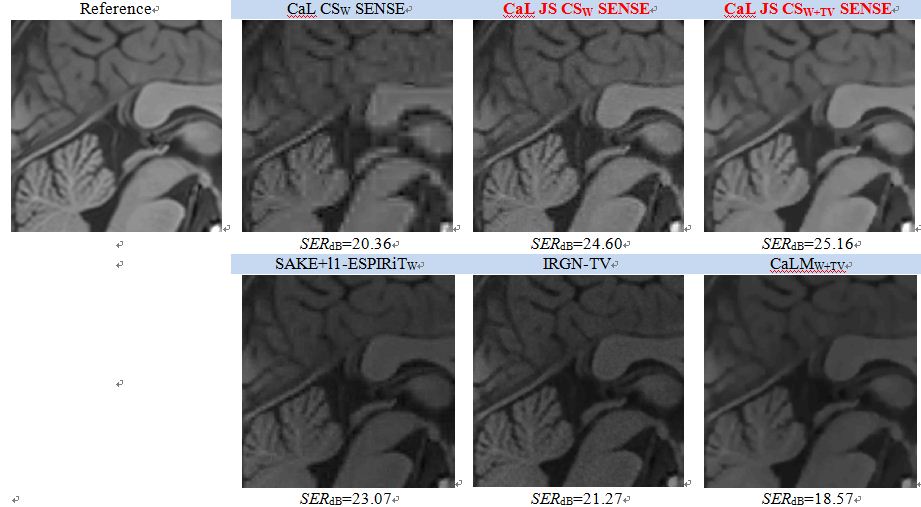

Figure: Calibration-less pMRI 영상 복원 기술들에 의해 복원된 영상들의 비교 (약 15%의 노이즈 섞인 k-space 데이타; 4개의 수신코일; 512x512의 영상 사이즈): 제안된 Calibration-Less (CaL) JS CS SENSE 기술은 다른 최신 기술보다 더 좋은 영상을 (1.9~6.6의 SERdB차이로) 복원하는 결과를 보여줍니다.

The theory and techniques of compressed sensing (CS) have shown their potential as a breakthrough in accelerating k-space data acquisition for parallel magnetic resonance imaging (pMRI). However, the performance of CS reconstruction models in pMRI has not been fully maximized, and CS recovery guarantees for pMRI are largely absent. To improve reconstruction accuracy from parsimonious amounts of k-space data while maintaining flexibility, a new CS SENSitivity Encoding (SENSE) pMRI reconstruction framework promoting joint sparsity (JS) across channels (JS CS SENSE) is proposed in this paper. The recovery guarantee derived for the proposed JS CS SENSE model is demonstrated to be better than that of the conventional CS SENSE model and similar to that of the coil-by-coil CS model. The flexibility of the new model is better than the coil-by-coil CS model and the same as that of CS SENSE. For fast image reconstruction and fair comparisons, all the introduced CS-based constrained optimization problems are solved with split Bregman, variable splitting, and combined-variable splitting techniques. For the JS CS SENSE model in particular, these techniques lead to an efficient algorithm. Numerical experiments show that the reconstruction accuracy is significantly improved by JS CS SENSE compared with the conventional CS SENSE. In addition, an accurate residual-JS regularized sensitivity estimation model is also proposed and extended to calibration-less (CaL) JS CS SENSE. Numerical results show that CaL JS CS SENSE outperforms other state-of-the-art CS-based calibration-less methods in particular for reconstructing non-piecewise constant images.

- Compressed sensing (CS, 압축센싱) 이론을 이용하여 SENSitivity Encoding (SENSE)을 기반한parallel MRI (pMRI)의 영상 복원 정확도를 향상시킨 논문입니다. 수신코일 영상간의 joint sparsity (JS)를 유도하는 본 기술(기술명: JS CS SENSE)은 기존의 SENSE를 기반으로 한 영상 복원 기술에 필요한 k-space 데이터 양을 줄일수 있으며, 여러개의 코일 영상을 복원하는 기술의 단점들(예: 수신코일 배치에 의한 영상 복원 제약, phase 정보 제거)을 극복할 수 있습니다. 이 외에도, JS CS SENSE 기술을 위한 효율적인 알고리즘을 제안하고 있을 뿐만 아니라, calibration 촬영의 도움 없이(calibration-less) 영상을 복원할 수 있는 방법을 소개하고 있습니다. 실제 영상으로 실험한 본문의 수치 해석은 최신기술들에 비해 최대 6.6dB signal-to-error ratio (SER) 향상된 바를 보여주고 있으므로, 국내외 MRI 관련 영상 복원 연구자들 및 방사선 전문의들에게 소개될만한 유용한 논문이라 생각합니다.